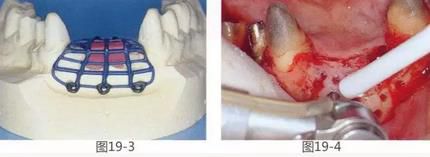

360截圖20170422142144525.jpg

圖19-1  將左下1,2,右下1,2拔除后4個(gè)月的正面照。

圖19-2  同時(shí)期咬合面照。佩戴臨時(shí)修復(fù)體后,由于易滯留食物殘?jiān)?,涂抹口紅困難而感到不滿。

360截圖20170422142155476.jpg

圖19-3  經(jīng)判斷,若在該病例中使用覆膜和骨移植材料并用的GBR法,就會(huì)使新生骨的形成量產(chǎn)生局限性。因此,使用了以黃金框架為支柱的GBR法,以防止覆膜脫落。事先進(jìn)行取模,用蠟片制作出預(yù)計(jì)的骨量和骨形態(tài),并在此基礎(chǔ)上進(jìn)行上蠟,鑄造黃金框架。

圖19-4  為了確保血液供給而進(jìn)行了皮質(zhì)剝除術(shù),這時(shí)通過OCT采集自體骨。